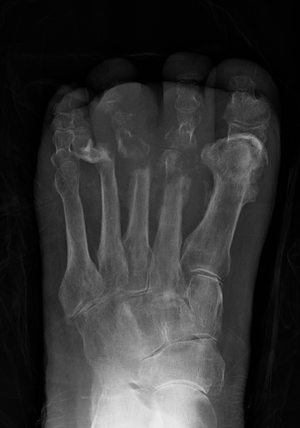

Osteomyelitis of the 1st toe | |

Radiographs and CT are the initial method of diagnosis, but are not sensitive and only moderately specific for the diagnosis. They can show the cortical destruction of advanced osteomyelitis, but can miss nascent or indolent diagnoses.[23]

Diagnosis of osteomyelitis is often based on radiologic results showing a lytic center with a ring of sclerosis.[13] Culture of material taken from a bone biopsy is needed to identify the specific pathogen;[27] alternative sampling methods such as needle puncture or surface swabs are easier to perform, but cannot be trusted to produce reliable results.[28][29]